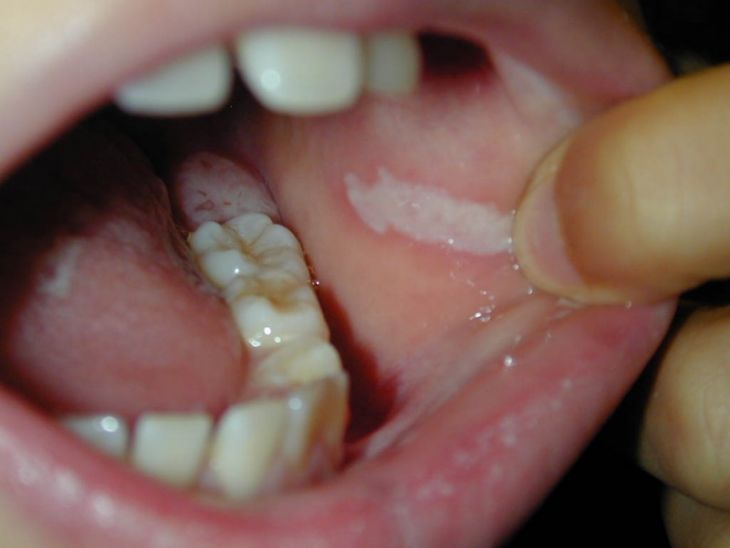

Фото лейкоплакии

Участок поврежденных поверхностей выглядит как гиперкератозная пятнистость – нестандартного разрастания внешних слоев, визуально определяющиеся как измененный эпителий мутного цвета, с четким разграничением.

Место воспаления напоминает ожоговые поражения слизистой оболочки (при неверном пользовании ляписным карандашом) или тонкую бумагу. Попытки соскоблить нестандартные слои остаются безрезультатными – налет крепко держится на месте.

Уровень повреждения тканей может быть разной интенсивности, на его фоне цветовая окраска пятен от сероватого до молочно-белого оттенка. Участки, затронутые аномальным процессом, шероховатые и сухие. При пальпаторном исследовании уплотнения не обнаруживаются, внешних признаков воспаления не существует.

Симптоматическим проявлением болезни служит разрастающееся ороговение, вызывающее значительное увеличение и утолщение верхних слоев слизистых покровов. Участки веррукозного поражения находятся выше рядом расположенных тканей, отличаются резким цветовым оттенком. Пальпаторное исследование подтверждает наличие поверхностного уплотнения.

- бляшечный вариант поражения – с образованием наростов белоснежного или желтоватого оттенка, имеющих четкие очертания и возвышающиеся над остальными мягкими тканями;

- бородавчатый – визуально определяется как бугристые образования серовато-беловатого окраса, с плотной консистенцией и размерами до 3 мм в высоту.